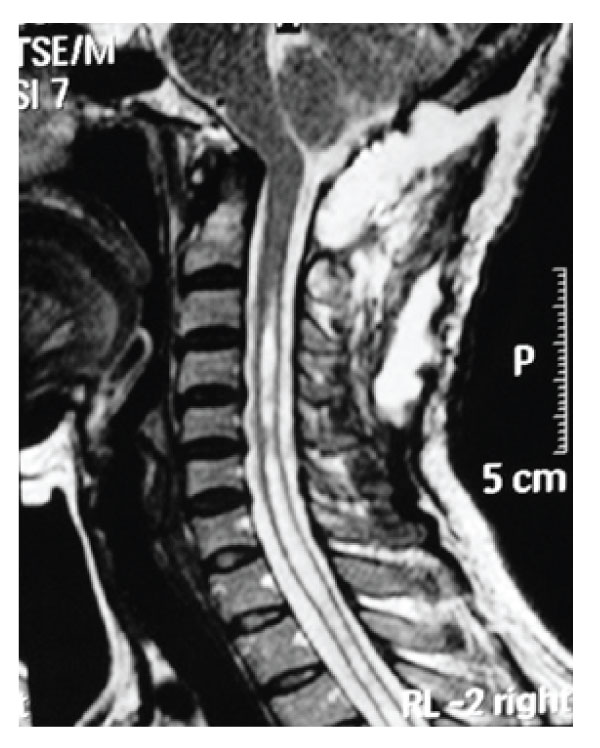

A 48 years old woman presented with a 5-year history of progressive headache and numbness on her upper extremities. She also suffered from weakness in both hands and gait disturbance. Her symptoms became worse over a 6 months period before admission. Neurological examination revealed slight quadriparesia with tendon hyperreflexia on the upper and lower extremities. Under C6 level, paresthesia and decreased temperature sensation without muscle atrophy were detected. MRI revealed a small posterior fossa with C4-Th6 syringomyelia without tonsillar herniation [Figure-5]. In CT scan of craniovertebral junction, short basis of occiput and short clivus with increased angle of tentorium was detected [Figure-6]. Dynamic plain films of the patient did not demonstrate instability. The patient was treated via posterior fossa decompression with C1 laminectomy and duraplasty. Intraoperative exploration disclosed no intradural adhesions. However, CSF flow was observed following dural opening. Postoperative period was uneventful and symptoms were gradually improved. Three months after the surgery the control MRI revealed decreased syringomyelia under C4 level [Figure-7].

Figure 6: Case 2 Pre-operative Sagittal CT scan showing short clivus and short basis occiput associated with small posterior fossa.

Figure 7: Case 2 Post-operative T2 weighted sagittal MRI demonstrating resolution of the syringomyelia.